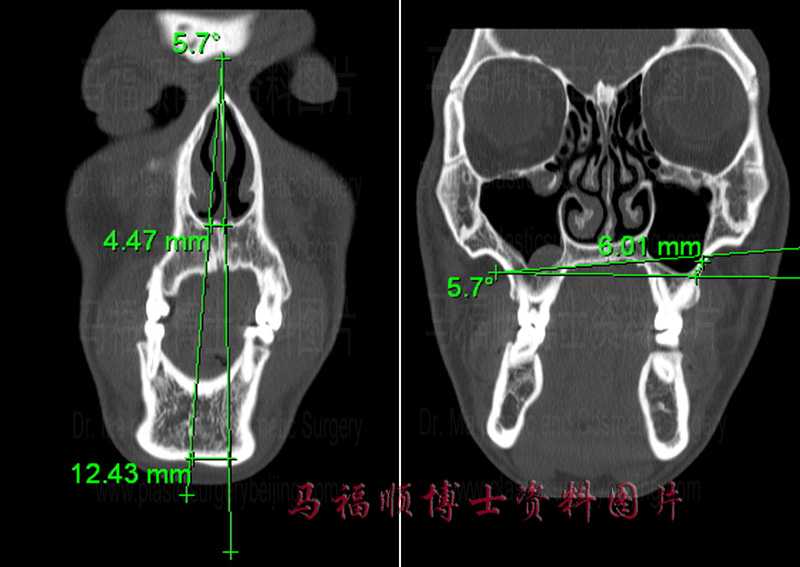

偏颌CT,上下颌骨中线偏离垂线,上颌骨的咬合面也不再水平。

颌面骨CT片上可以更加精确地测量面部中线的成角与偏斜程度。同样左侧CT片中右侧的竖线为面部垂线,左侧者为下颌骨的中缝线。这两条线的夹角约为5.7度,在下巴颏水平,下颌向左侧的偏移距离为12.5MM,在鼻基底平面,上颌骨的偏移距离约为4.5MM。右侧CT片示上颌骨在水平面上的偏斜程度,使咬合面变水平所需要将左侧上颌骨的高度缩短的距离约为6MM。